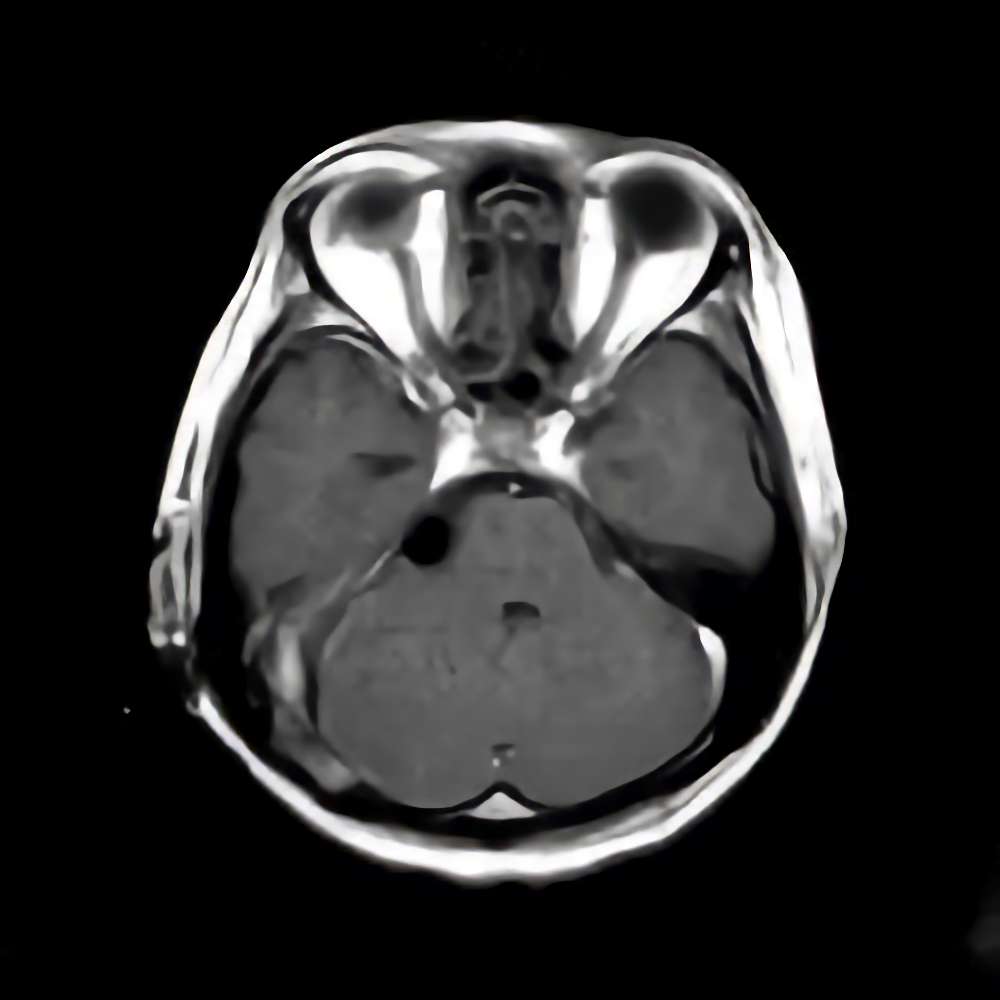

134

'19年10月

70代

左側頭葉膠芽腫

頭蓋内腫瘍摘出術

No.’19_35 手術前1

No.’19_35 手術前2